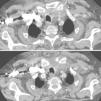

Case 4. Male 75 years, allergic to beta-lactams, diagnosed with actinic proctitis. He consulted for rectal bleeding, fever of 39° C and pain in the cervical region for 2 days. In the ER he developed erythema and edema, as well as pain on palpation of the anterior cervical region. A cervical CT angiography determined swelling of the sternoclavicular joint and the sternocleidomastoid, with protrusion into the premediastinic space (Fig. 1) contacting the brachiocephalic vein. In the SF, Staphylococcus aureus was isolated.

Case 5. Male 55 years. He consulted for a painful swelling of the left chest, of 24h of evolution. Four days before he consulted for atraumatic left shoulder pain. He presented erythematous and painful swelling of the sternoclavicular joint, fluctuating and with sharp edges. Ultrasonography showed capsular distension and PDS (+) both intracapsular as extracapsularly. A superficial abscess of the joint was also identified. A CT scan confirmed the findings and also detected involvement of the distal clavicular sternocleidomastoid body (Fig. 2 Surgical drainage was required. S. aureus was isolated in the culture.